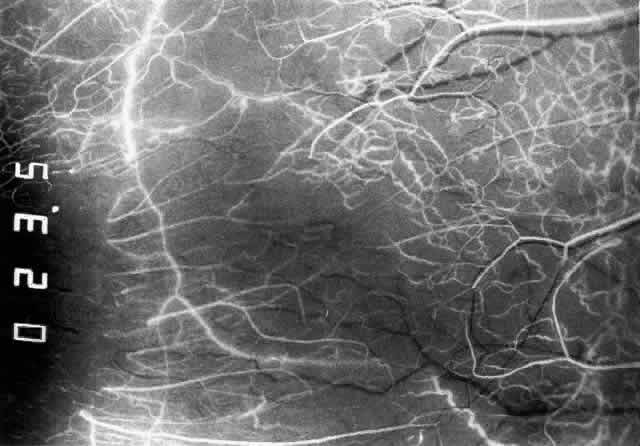

The characteristic features of necrotizing scleritis on fluorescein angiography

are hypoperfusion and, eventually, nonperfusion of the vascular

networks (Figs. 40 through 43).26 The initial changes are on the venous side of the capillary network; the

transit time of the dye increases even if the eye is red and congested. If

the disease process persists or has been present for a long time, thrombosis

and permanent vaso-occlusive changes occur. These vessels (or

the occluded capillary network) are bypassed by the opening of

anastomotic channels. New vessels in a granuloma give rise to deep intrascleral

leakage of dye (see Fig. 43). Conjunctival and episcleral involvement by the destructive change is

Fig. 41. Late stage of fluorescein angiogram adjacent to the site of necrosis in

the same patient as in Figure 40. Although the eye is uniformly congested, the area near the necrosis shows

vascular shutdown, whereas the rest of the conjunctiva and episclera

is normally perfused. Fig. 41. Late stage of fluorescein angiogram adjacent to the site of necrosis in

the same patient as in Figure 40. Although the eye is uniformly congested, the area near the necrosis shows

vascular shutdown, whereas the rest of the conjunctiva and episclera

is normally perfused.

Fig. 42. Late arterial phase of fluorescein angiogram in a patient with necrotizing

scleritis. All the vessels except the main trunk and the vessels around

the limbal perforating vessels are occluded and remain unperfused

throughout the angiogram. Fig. 42. Late arterial phase of fluorescein angiogram in a patient with necrotizing

scleritis. All the vessels except the main trunk and the vessels around

the limbal perforating vessels are occluded and remain unperfused

throughout the angiogram.

Fig. 43. Late venous phase of angiogram of a patient with necrotizing scleritis

showing late deep leakage from vessels on the surface of the sclera and

leakage of the capillary network at the limbus and the vessels draining

it, together with poor or absent perfusion of the remaining vessels. Fig. 43. Late venous phase of angiogram of a patient with necrotizing scleritis

showing late deep leakage from vessels on the surface of the sclera and

leakage of the capillary network at the limbus and the vessels draining

it, together with poor or absent perfusion of the remaining vessels.